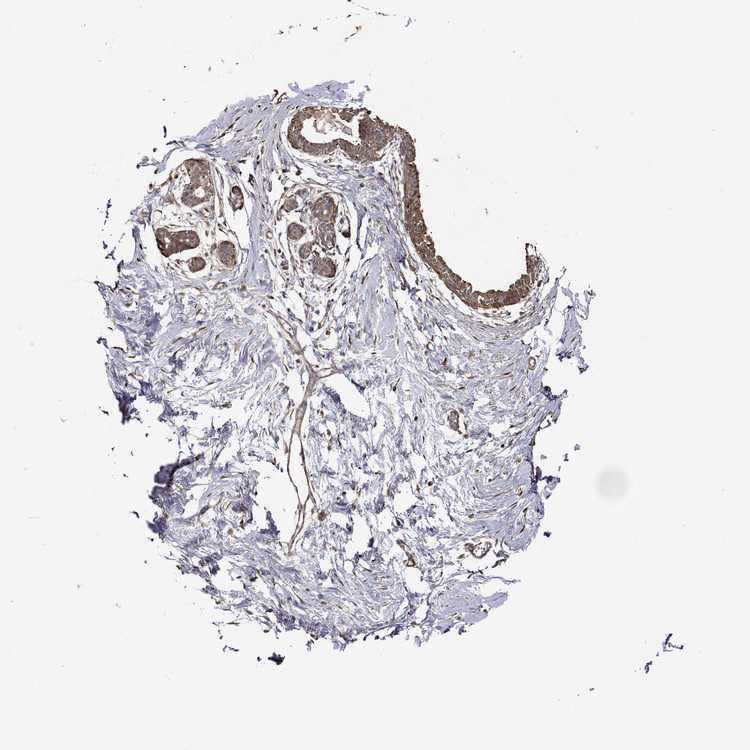

BREAST - Antibody stainingi

Antibody staining in the annotated cell types in the current human tissue is reported as not detected, low, medium, or high, based on conventional immunohistochemistry profiling in selected tissues. This score is based on the combination of the staining intensity and fraction of stained cells.

Each image is clickable and will lead to virtual microscopy that enables deeper exploration of all samples and also displays staining intensity scores, fraction scores and subcellular localization as well as patient and tissue information for each sample.

Antibody HPA069107

Adipocytes Medium

Glandular cells Medium

Myoepithelial cells High